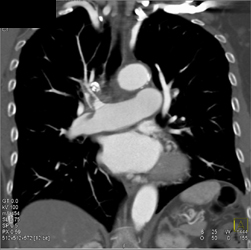

Cystic Fibrosis